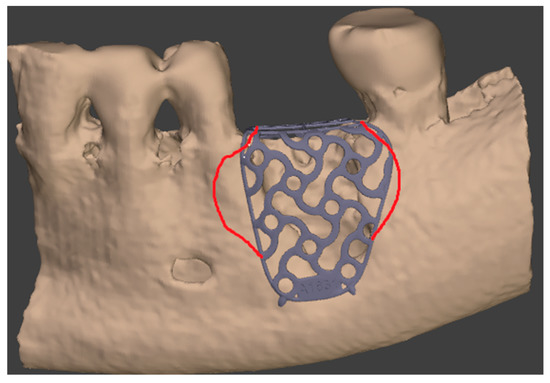

- Flap design: Soft tissue management should be as accurate as possible. The design of the flap should ensure a tension-free primary closure of the wound even after voluminous grafting of the defect. One option (preferred especially in wide vertical defects) is the execution of the so-called “poncho” flap. This technique includes a high vestibular incision of the mucosa, muscle and periosteum in order to undermine the preparation of the flap and to achieve its mobilization, followed by a deep incision in the buccal area with two additional vertical incisions that are performed at an appropriate distance from the occlusal area and the site of augmentation. After the incision, the preparation of a muco-periosteal flap and the remotion of scar tissue, a full thickness flap is raised until the bone defect is uncovered [17,18,19,20]. Finally, the positioning of the customized titanium mesh is passively tested to evaluate its fit intra-operatively (Figure 2, Figure 3, Figure 4 and Figure 5).

- Positioning of the customized titanium mesh: Being patient-customized or responding to the specific requirements of the patient in terms of planned bone augmentation, this mesh does not require any modification and it should perfectly fit the patient’s residual bone (Figure 8).